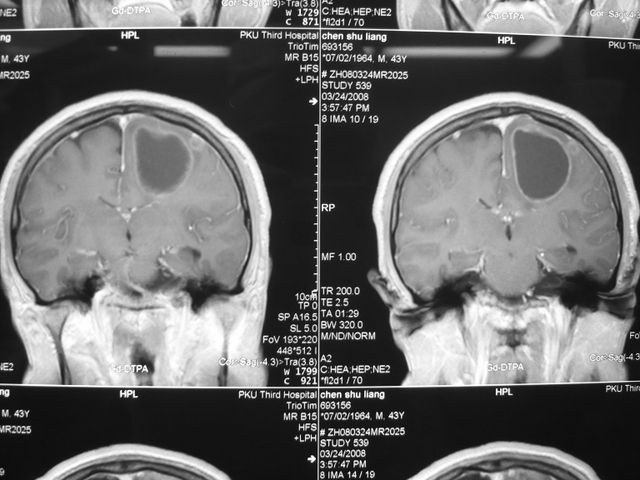

肺癌脑转移Omaya囊置入术

肺癌脑转移Omaya囊置入术肺癌脑转移Omaya囊置入术